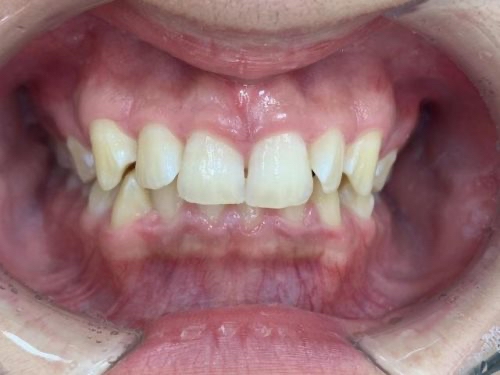

拝見したところ、噛み合わせた時に上の前歯が覆いかぶさり、下の前歯がほとんど見えないほど噛み合わせが深い「過蓋咬合(かがいこうごう)」が認められました。

また、上左右の前歯(側切歯/2番)と右下の前歯(犬歯/3番)は、捻れて生える「捻転(ねんてん)」が見られました。